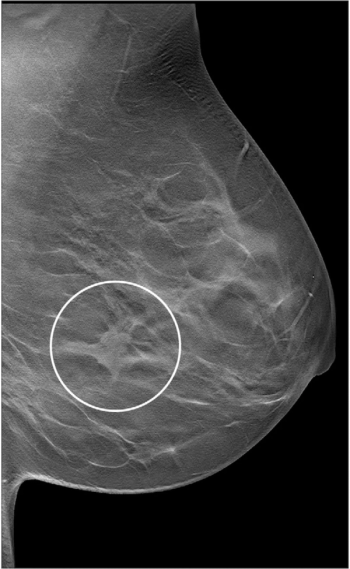

Contrast-enhanced mammography detected additional lesions in 43 percent of patients and led to additional biopsies in 18.2 percent of patients, over half of whom had malignant lesions, according to a study of over 500 women presented at the recent Radiological Society of North America (RSNA) conference.

The combination of digital breast tomosynthesis (DBT) and digital mammography had a 21.6 higher invasive breast cancer detection rate for stage 1 tumors than digital mammography alone, according to a new study involving nearly 100,000 women.